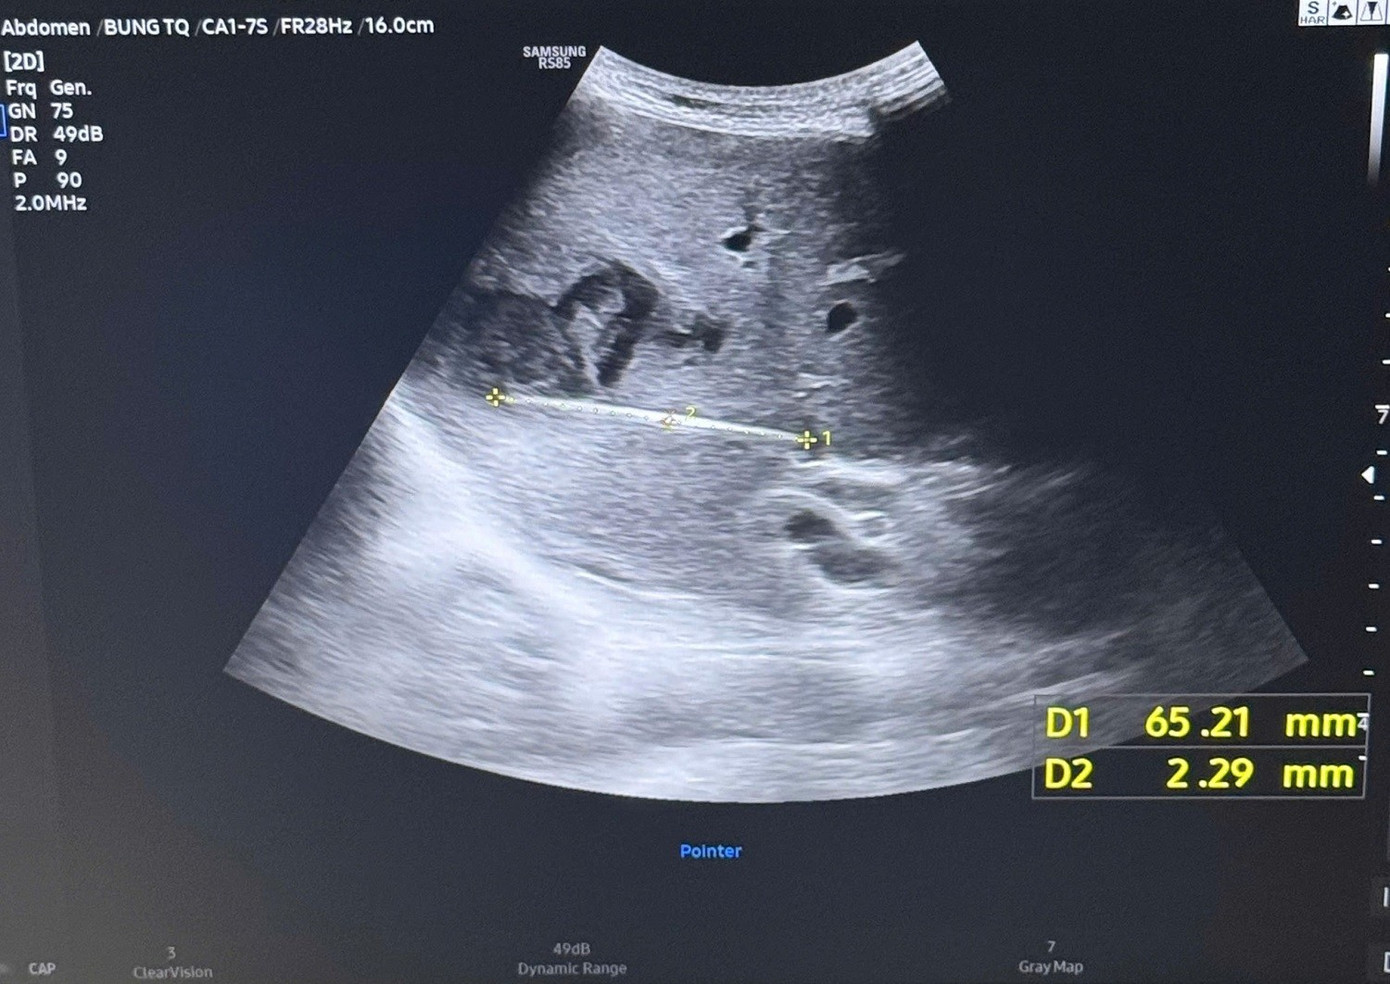

Qua siêu âm kiểm tra và chụp CT ổ bụng, các bác sĩ phát hiện một tổn thương bất thường trong gan với hình ảnh dị vật dài khoảng 7 cm nằm hoàn toàn trong nhu mô gan, kèm theo ổ áp xe sâu.

Hình ảnh kiểm tra phát hiện dị vật xuyên thấu vùng gan của người bệnh gây áp xe nghiêm trọng